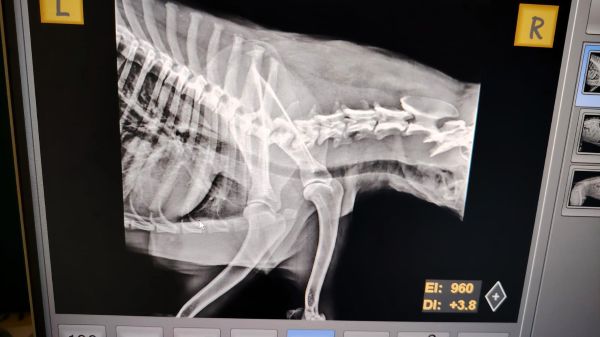

MATEI wurde vom Auto angefahren und am Straßenrand einfach liegen gelassen. So wurde er heute gefunden. Bei der Untersuchung kam heraus, dass seine Wirbelsäule verletzt ist. Die Ärzte sind zuversichtlich, dass man ihm mit einer Operation helfen kann und seine Verletzungen heilen werden. Daher wurde er nun in die Tierklinik nach Bukarest gebracht.

| zur Besonderheit: | hatte Autounfall, aktuell in Clinic |